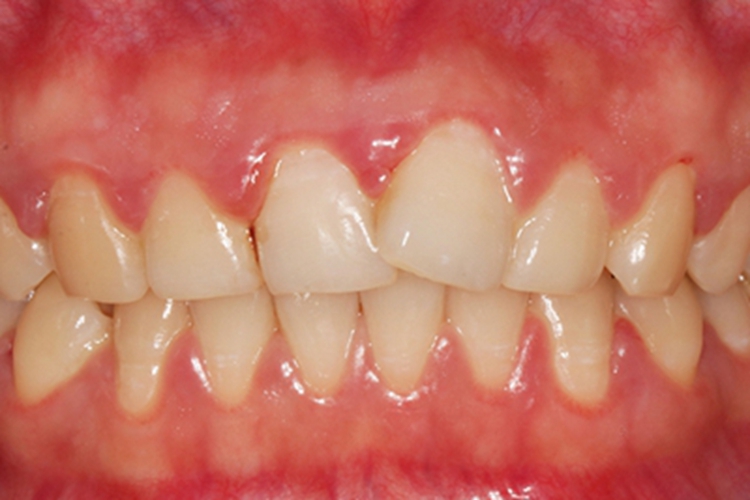

慢性龈炎牙龈肿胀,呈红色改变,表面完整光滑,龈乳头圆钝肥大,可呈肉球状凸起。

慢性龈炎的病损部位一般为牙龈的游离龈和龈乳头,游离龈和龈乳头颜色变为鲜红或暗红色,表面完整、光滑,病变较重时炎性充血、肿胀可波及附着龈。龈缘变厚,龈乳头圆钝肥大,可增生呈肉球状凸起,覆盖牙面。牙龈松软脆弱,缺乏弹性。